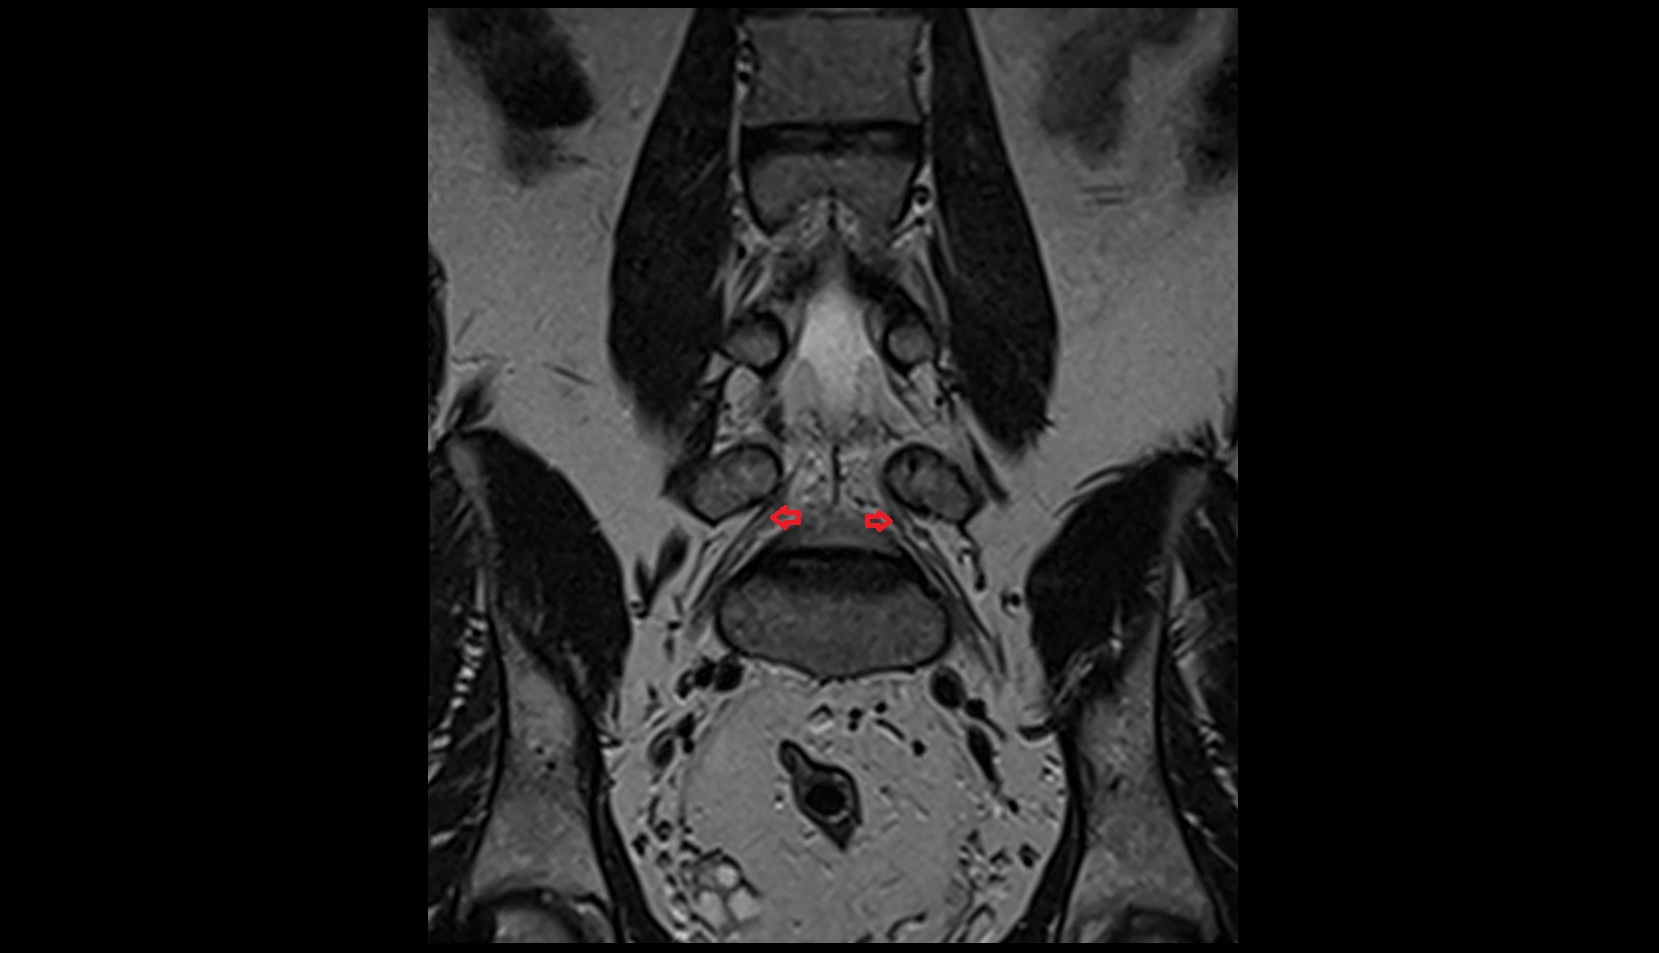

- Peripheral zone of prostate

- Anterior Fibromuscular Stroma of prostate

- Central zone of prostate

- Transitional zone of prostate